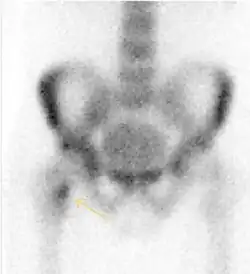

Nuclear Medicine

Bone scanning in people with hip pain can be complementary to other imaging studies, mainly in indeterminate bone lesions to clarify whether it is an active lesion with abnormal radiotracer accumulation. Nevertheless, MRI has replaced scintigraphy in the diagnosis of most of these conditions. An example is stress or insufficiency fractures: increased uptake is usually present in around 80% of fractures within 24 h, and 95% of fractures reveal activity by 72 h following trauma, showing an overall sensitivity of 93% and specificity of 95%. MRI is superior to bone scans in terms of sensitivity (99%-100%) and specificity (100%). Moreover, a bone scan does not provide detailed anatomical location of the fracture, and further imaging is usually required.[1]

MRI has been shown to have 100% sensitivity and specificity in prospective studies of occult hip fractures. These fractures were diagnosed by bone marrow edema and a low signal fracture line, mainly on T1 or T2 weighted images (Figure 10).[1]

Stress femoral neck fracture in a young athlete barely visible in X-ray film as a sclerotic line (arrow)[1] -

In this case, Tc 99 scintigraphy shows a band of uptake[1] -

Furthermore, T1 (left) and DP fat saturated (right) weighted MR images showed the fracture line and a pattern of edema.[1]